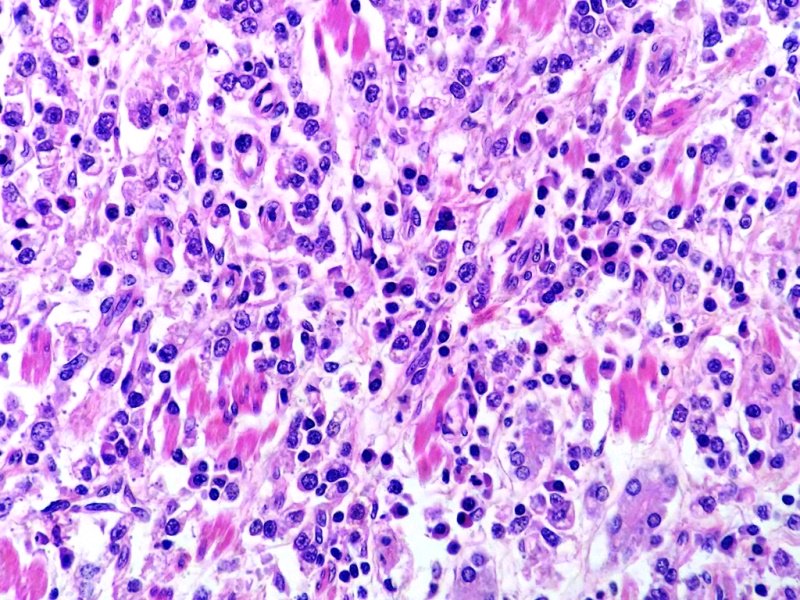

Estómago. Adenocarcinoma gástrico difuso con estroma linfoide. Tinción HE